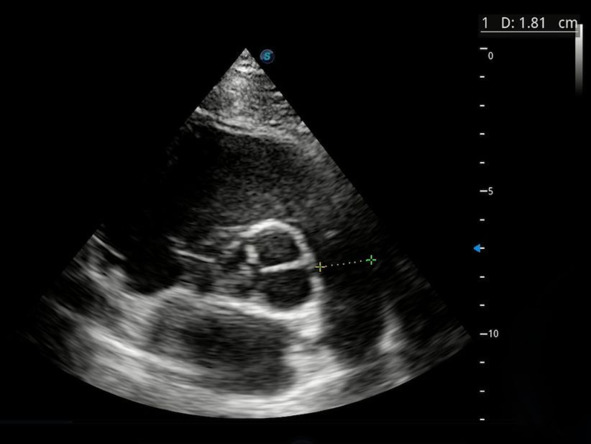

Снова возвращаемся в парастернальную позицию по короткой оси на уровне аорты. Наша задача – измерить диаметр легочного ствола, на рисунке 10 он составляет 1,81 см.

Рис. 10